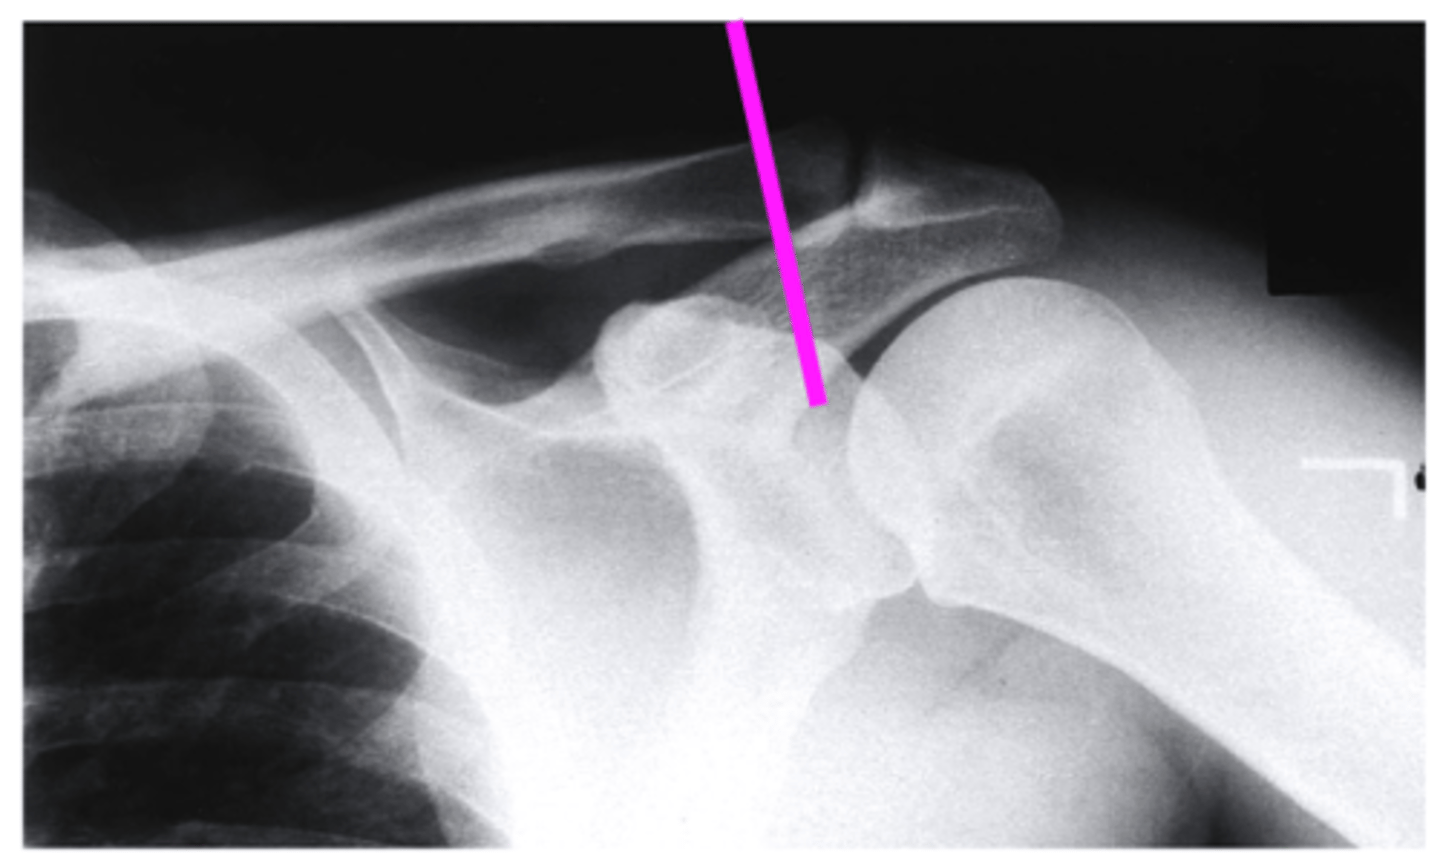

scapular Y lateral

what view is this

clavicle

what does the pink line point to?

coracoid process

acromion of scapula

humeral head

inferior angle of scapula

body of scapula